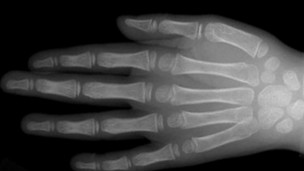

تركيبة قبضة اليد تعزز من قدرة المفاصل على نقل قوة "اللكمة".

وتوصلوا إلى أن تركيبة قبضة اليد تعطي دعما يزيد من قدرة المفاصل على نقل قوة "اللكمة".

وتوصل فريق البحث أيضا إلى أن القبضة الثابتة تعزز بالفعل حماية عظام اليد الرقيقة. فضم القبضة يزيد لأربعة مرات من صلابة المفصل السنعي السلامي الثاني، وتلك هي المفاصل التي تظهر على الأصابع عند عمل قبضة اليد.

كما أنها ضاعفت من قدرة عظام الأصابع، التي ترتبط بالمفاصل السنعية السلامية، على نقل قوة اللكمة.

ضم القبضة يزيد لأربعة مرات من صلابة مفاصل الأصابع